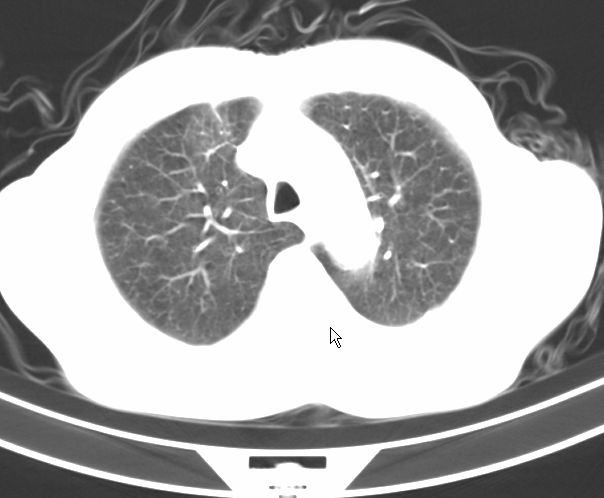

请大家看看是什么性质的。炎性病变首先考虑哪一种炎症。

支持右肺上叶前段\\下叶内基底段感染,建议抗炎治疗后复查,除外结核.

支持右肺上叶前段\\下叶上段感染,建议抗炎治疗后复查,除外结核.

支持右肺上叶前段、下叶内基底段感染,建议抗炎治疗后复查,除外结核.

右肺上叶前段及下叶内基底段感染性病变;建议抗炎治疗后复查。

楼主说是炎症,凭啥?典型的周围型肺癌(腺癌可能性大),肝内可能已有转移,强化看看吧。